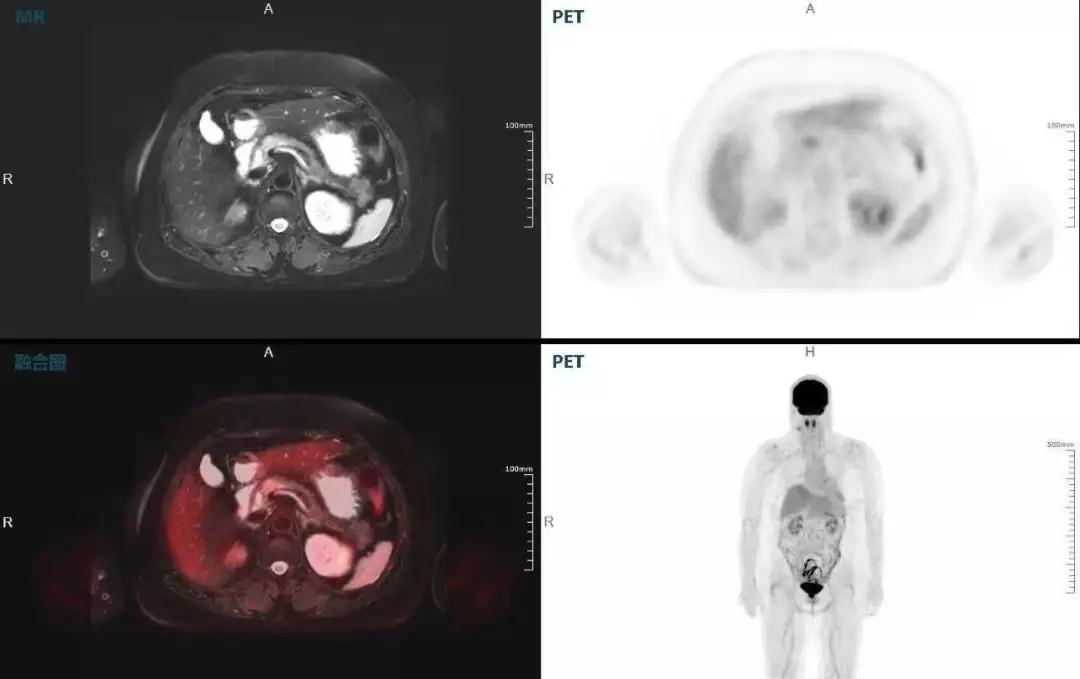

胰腺癌

中山醫(yī)院核醫(yī)學科在臨床實踐中發(fā)現(xiàn),基于聯(lián)影“時空一體”超清TOF PET/MR,不僅解剖信息和代謝信息能夠完美融合呈現(xiàn),同時精細展示局部病灶與周圍組織的復雜關系,并能全盤檢測病灶的全身轉移,為醫(yī)生臨床診斷提供更豐富信息。

(胰腺腫瘤,MR顯示胰腺體部信號異常,PET顯示稍高攝取,結構改變和功能異常提示胰腺MT可能大。)